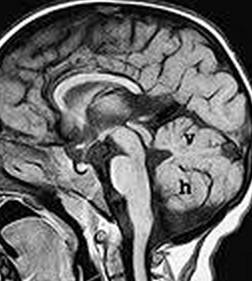

Sweep the Midline…Name the parts…where do we start?

Sag T2 Cube nongated Normal

Normal

Sag T2 Cube

Nongated: CSF dephasing in the aqueduct on this sequence

Primary fissure 3 lobes Closed fastigial point

Sag T2 Cube Normal

Anterior commissure

Corpus Callosum

Rostrum, genu, body, splenium

Sella/Suprasella

ON, post pit bright spot, stalk

Midbrain

Patent aqueduct

Pons

“just right…”

Vermis

3 lobes

Cerebellar Tonsils